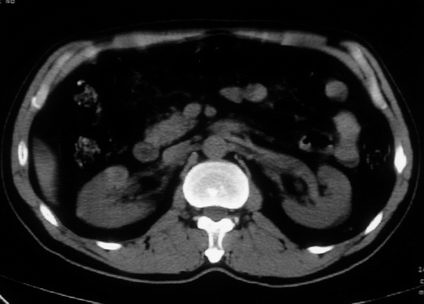

男,体查发现右肝低密度,右肾高密度结节影。高密度ct值92hu,囊肿?

肝右叶囊肿或血管瘤?右肾高密度囊肿。建议增强。

肝右叶圆形低密度灶,考虑囊肿或血管瘤,建议ct增强检查;右肾包膜下高密度圆形灶,考虑:囊肿并出血